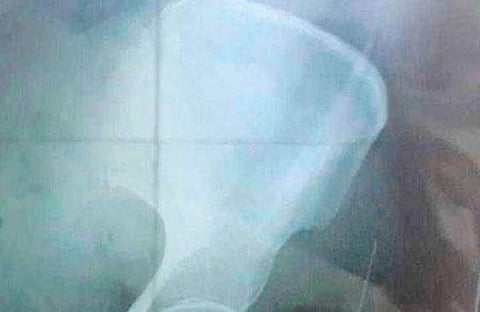

X-ray showing the needle body | EXPRESS

According to her son K Thirugnanasambandhamoorthy, officials from the GH visited them on November 13 and requested Parvathi to come for a  check-up. A second x-ray was taken and it revealed the needle had gone deep inside her body. The needle is about 21 mm in length and 1.2 mm in diameter. Since it could only be removed surgically, she was advised to go to Rajah Muthiah Medical College in Chidambaram or any other advanced hospital for surgery.